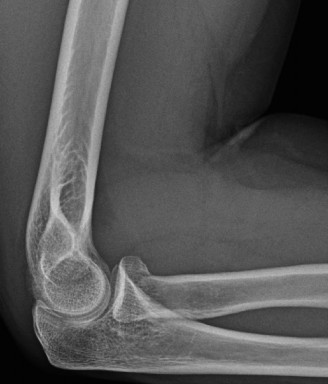

It should be noted that reverse total shoulder arthroplasty is also the procedure of choice in patients with cuff-tear arthropathy (aka rotator cuff arthropathy). Characteristics of cuff-tear arthropathy include superior migration of the humerus due to a massive rotator cuff tear, glenohumeral joint destruction, subchondral osteoporosis, and humeral head collapse (see Fig. 2–17). A reverse total shoulder

Figure 2–17_X-rays of a patient showing evidence of cuff tear arthropathy. The humerus is migrated superiorly, the glenohumeral joint is destroyed, there is subchondral osteoporosis, and the humeral head is collapsed. (From Ecklund KJ, Lee TQ, Tibone J, Gupta R. Rotator cuff tear arthropathy. _J Am Acad Orthop Surg. 2007;15(6):340–349.)